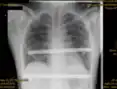

X-ray of a 15-year-old male after undergoing the Nuss procedure

In 1987, Donald Nuss, based at Children's Hospital of The King's Daughters in Norfolk, Virginia, performed the first minimally invasive repair of pectus excavatum (MIRPE) [53] and presented it much later at a conference in 1997.[53][54][55]

His two-stage procedure, widely known as the Nuss procedure, involves slipping in one or more concave steel bars into the chest, underneath the sternum.[56]

The bar is flipped to a convex position so as to push outward on the sternum, correcting the deformity. The bar usually stays in the body for about two years, although many surgeons are currently moving toward leaving them in for up to five years. When the bones have solidified into place, the bar is removed through outpatient surgery.